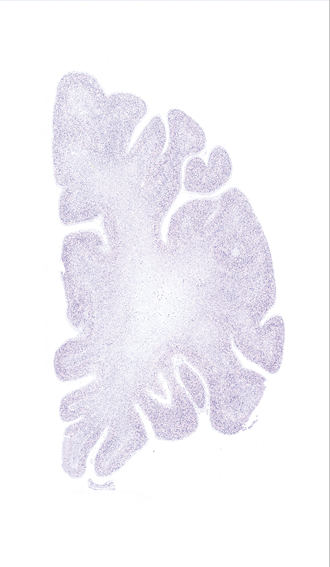

Hi-Resolution Sections · Cells (Nissl Staining) · Virtual Microscopy

Frontal sections (Nissl) from the Atlas Brain:

Slice ID:

r2-1027

Plate NR:

06

Position:

-30,6 mm